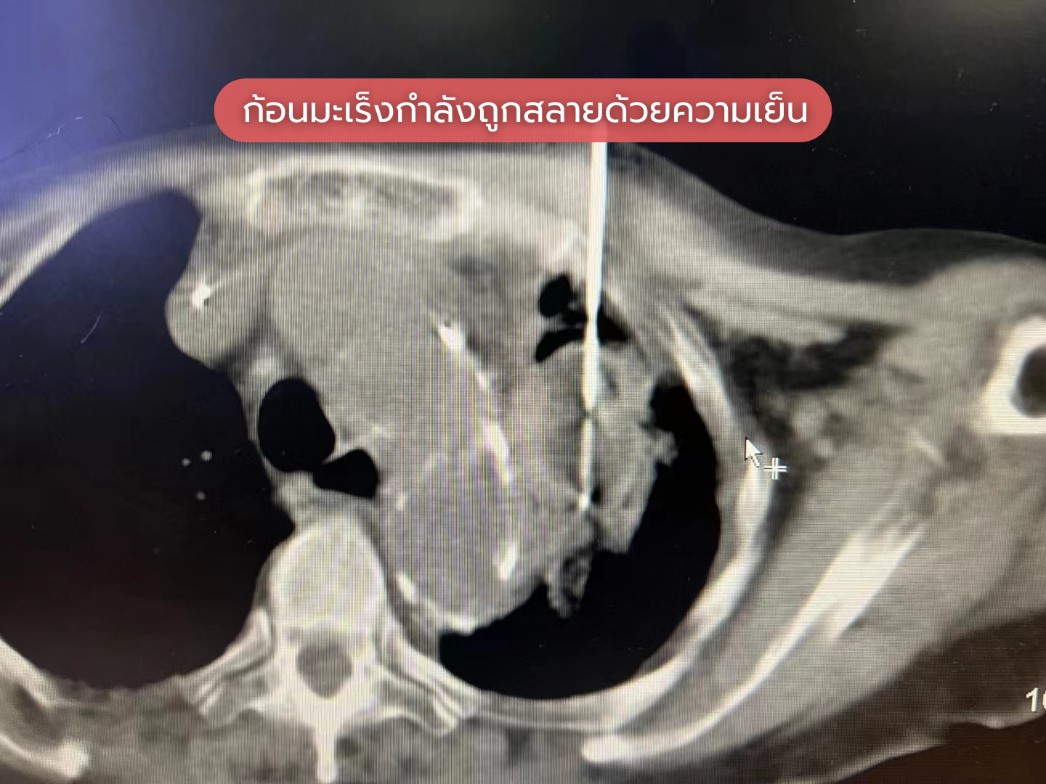

การสลายก้อนมะเร็งปอดด้วยความเย็น

ทีมแพทย์ของเราได้ทำการสลายก้อนมะเร็งปอดด้วยความเย็น พร้อมกับเจาะชิ้นเนื้อให้คนไข้ในคราวเดียวกัน โดยใช้เทคนิคพิเศษเพื่อหลีกเลี่ยงการกระทบกับเส้นเลือดแดงใหญ่